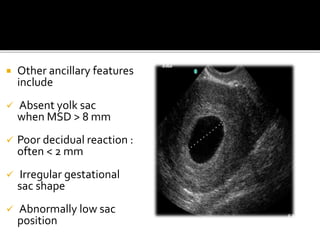

 Other ancillary features

include

 Absent yolk sac

when MSD > 8 mm

 Poor decidual reaction :

often < 2 mm

 Irregular gestational

sac shape

 Abnormally low sac

position